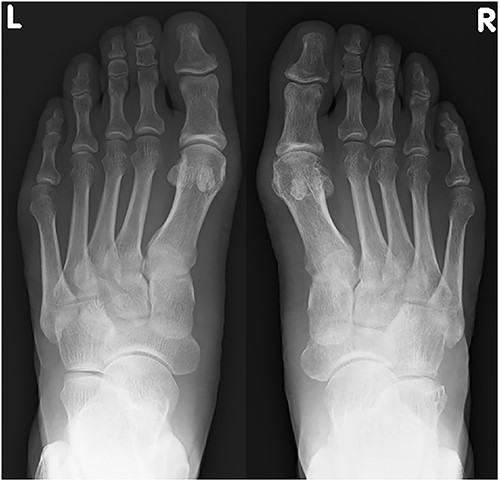

A plain radiograph shows lateral dislocation of the naviculocuneiform and calcaneocuboid joints of the right foot (arrow). The difference between the two sides is obvious.